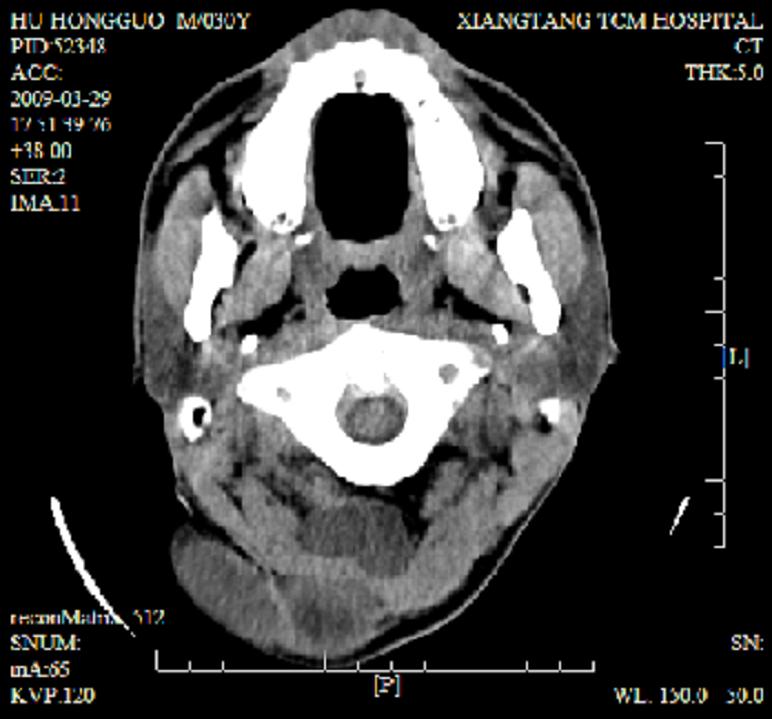

标题: CT19102:颈部肿块

男30y发现肿块3年

多处囊实性肿块,形态欠规则有一定形态,内见点状钙化,以囊变为主,增强后轻度强化,首先考虑神经源性肿瘤如鞘瘤,不除外脉管源性肿瘤如淋巴管瘤(见缝钻及囊性区域太多,如果合并感染完全可以这个影像表现),和海绵状血管瘤,但是血管瘤不太支持因为强化特征和病灶形态不典型.

右侧椎前间隙后部肌间、皮下囊性为主病变,可见分隔和点状钙化,分隔和壁呈轻度环形强化,大部分无强化。形态不规则,有钻缝特点。考虑1 淋巴管瘤合并感染2 血管平滑肌脂肪瘤3 表皮样囊肿4 不除外海绵状血管瘤。

病灶沿皮下及肌间隙爬行,病灶内有钙化灶,病灶有强化。病史3年,病人应该没什么症状。考虑纤维血管瘤可能性大。